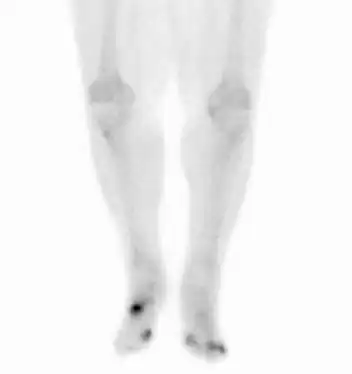

Osteomyelitis in both feet as seen on bone scan